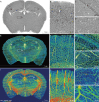

Figure 4.

Quantitative comparison of the hippocampal vasculature between WT and Tg-AD mice. (A) and (B) The same sections as shown in Fig. 3G and H are displayed with somata, vessels and nerve processes together to facilitate the demarcation of hippocampal sub-regions. The hippocampal vasculatures were divided into four subareas based on the hippocampal functional partition including the subiculum (Sub), CA1–2, CA3 and molecular layer of the dentate gyrus (DG-ml). The quantitative analyses of the main morphometric parameters were conducted on the basis of these segmented sub-regions. (C–F) Quantitative analysis of the hippocampal vascular network. Columns and boxes in blue are the WT group; columns or boxes in red are the Tg-AD group. (C) Comparison of the mean diameter, volume fraction and length density in the whole hippocampus between WT and Tg-AD mice (unpaired t-test; *P < 0.05; ***P < 0.001; ns, non-significant, P > 0.05; n = 3 mice per group). (D–F) Comparison of the mean diameter, volume fraction and length density in the four segmented sub-regions between the WT and Tg-AD mice (unpaired t-test; *P < 0.05; **P < 0.01; ***P < 0.001; ns, non-significant, P > 0.05; n = 2 sections per mouse for three WT mice and three Tg-AD mice). Error bars in (C) represent s.e.m.; error bars in (D–F) represent the greatest value (above) and lowest value (below).